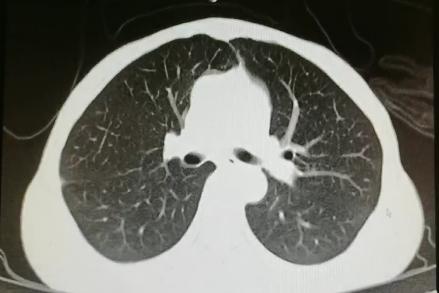

胸部CT:

右肺感染吸收,双侧胸腔积液吸收,双肺散在小结节,多系炎症,左膈抬高。

患者青年女性,慢性病程;主要表现为腹胀、呼吸困难,术后出现意识障碍、II型呼吸衰竭。经呼吸机辅助呼吸、对症支持等治疗后,患者意识恢复但呼吸困难无明显改善;既往有有粉尘接触史。查体见患者极度消瘦、营养不良,双肺呼吸音粗,可闻及散在湿啰音。血气示II型呼吸衰竭、高碳酸血症,轻度贫血,低蛋白血症,电解质紊乱,炎症指标、肌酶、BNP升高,院外腹水检查示漏出液,未见肿瘤细胞;胸部CT:双肺斑片影,抗感染治疗后病灶吸收;腹部增强CT:双侧附件区分别混杂密度团块影,内见多发囊泡影;心脏彩超:右心稍大,重度肺动脉高压。